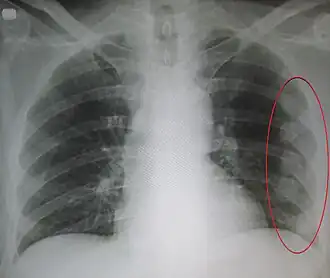

Description de cette image, également commentée ci-après

Radiographie de multiples fractures costales gauches (entourées d'un ovale)